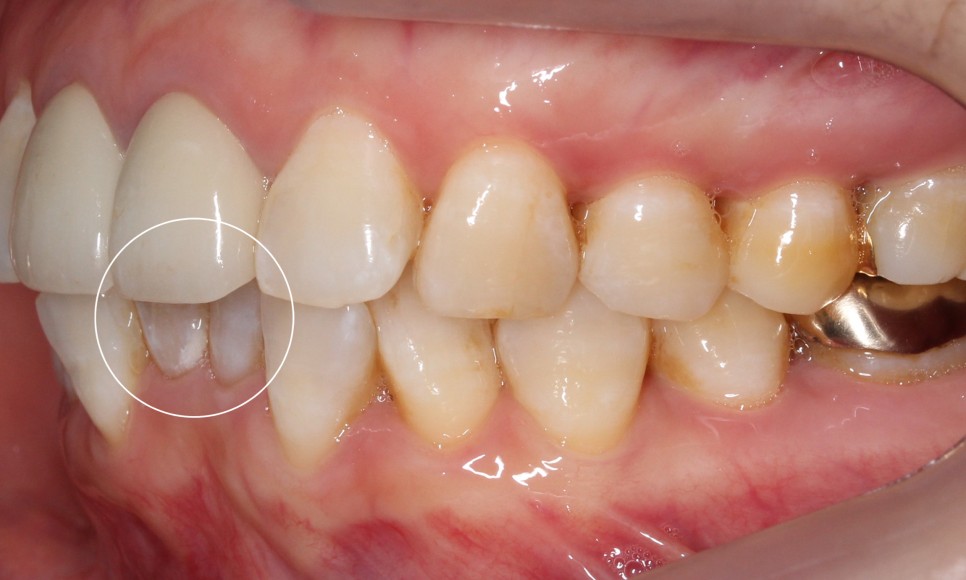

위 사진을 보시면

환자분의 아랫니 상태가

심하게 삐뚤거리는 모습을

확인할 수 있습니다.

치아 사이의 공간이 좁아서

작은앞니의 각도가

심하게 회전된 모습인데요.

측면을 보시면

아랫니의 앞쪽이 윗니의 뒷쪽으로

많이 들어가 있는 것을